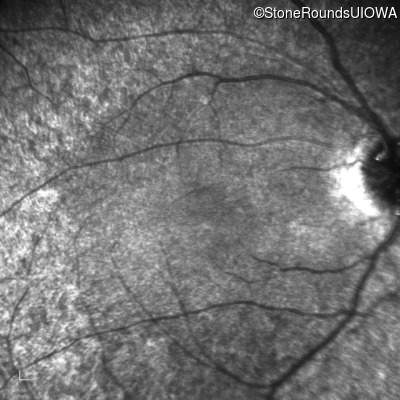

Age at visit: 15 years

This 15 year old male has had very poor vision and nystagmus since the first year of life.